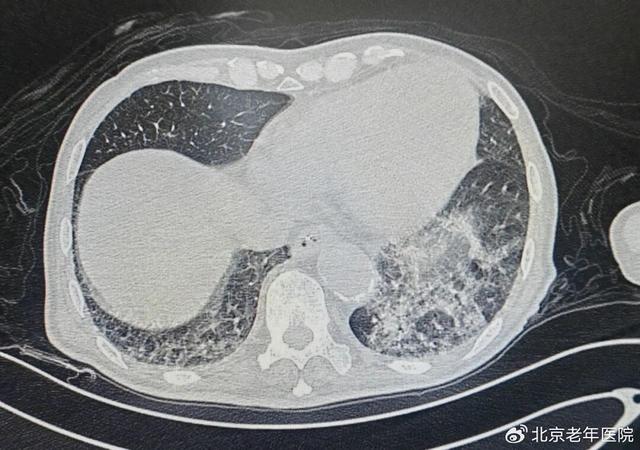

为明确病因并制定针对性治疗方案,呼吸内科刘前桂主任医师为患者进行了床旁气管镜检查。检查中发现,患者气道内积聚大量脓痰,尤其左下肺区域的痰液粘稠度极高,难以直接吸出。刘前桂主任医师团队随即采用生理盐水反复冲洗气道,随着视野逐渐清晰,一个异物的轮廓在左下叶基底段支气管内显现——这正是导致高先生反复感染的“罪魁祸首”。

11月21日上午,手术在充分的镇静与镇痛保障下正式开始。吴海玲副主任医师操作气管镜,凭借丰富的临床经验,先逐步吸除气道内残留痰液,彻底暴露异物位置。术中清晰可见,异物为一颗形态细长的脱落牙齿,深深嵌顿在直径仅约2mm的左下叶后基底段支气管远端,周围还包裹着大量分泌物,手术难度远超常规气道异物取出术。